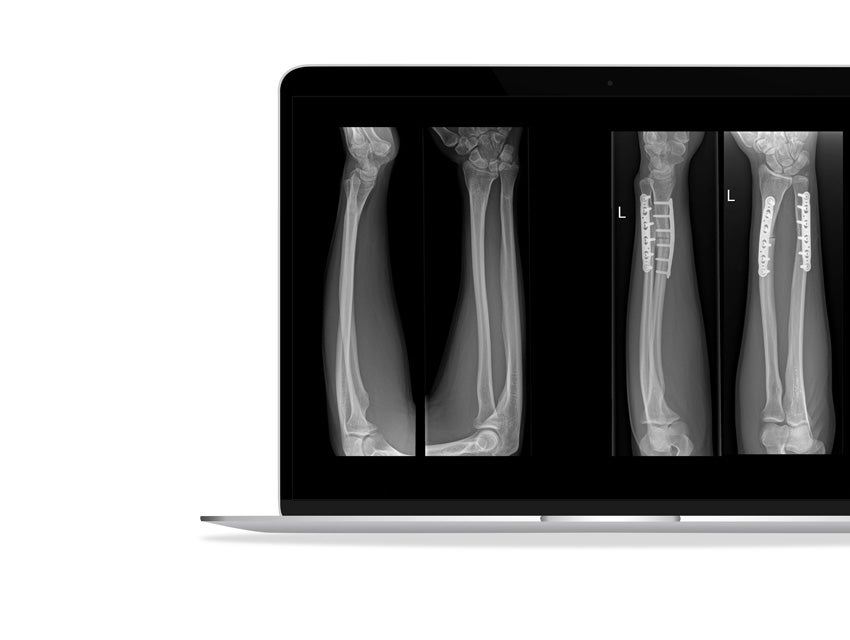

The focus of this webinar is 3D planning for forearm malunions, which is frequently comprised of complex deformities, often not perfectly visible on 2D images from X-rays.

- How 3D technology can improve pre-surgical assessment

- How personalized guides can help increase the accuracy of the osteotomy